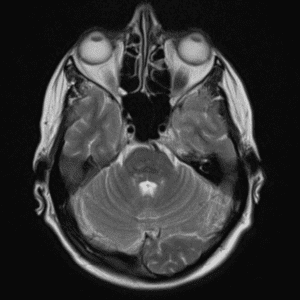

Case #5

Neurofibromatosis type II